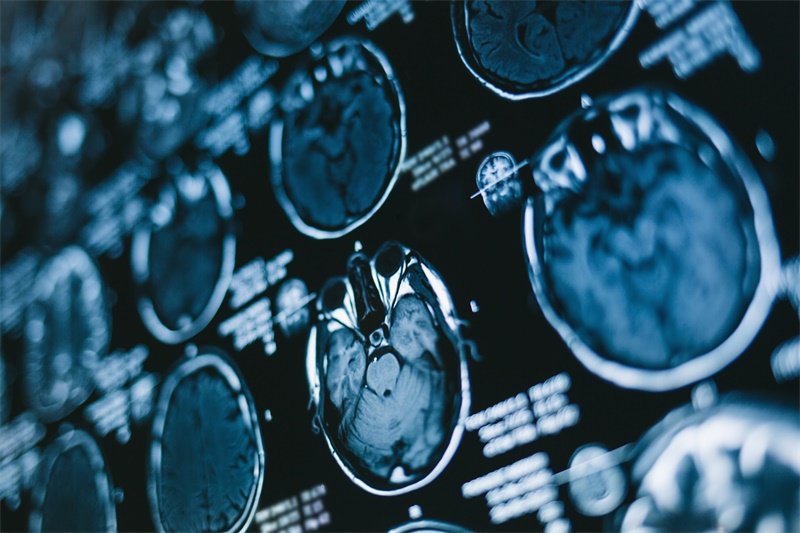

影像学检查

磁共振成像(MRI)是最常用的影像学检查方法。MRI可以清晰地显示出病变的位置、大小和性质,帮助医生做出准确的诊断。